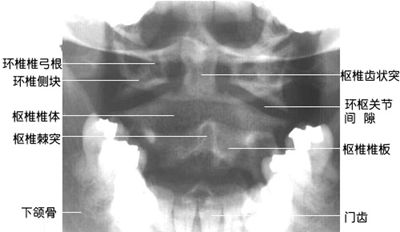

图6-1 颈椎正位DR平片

1 齿状突 odontoid 2 钩椎关节 uncovertebral joint

3 第5/6颈椎间隙 5th/6th cervical intervertebral space

4 第7颈椎横突 7th cervical transverse process

5 第1胸椎椎体 1st thoracic vertebral body 6 第1肋骨 1st rib

7 棘突 spinous process

8 第5颈椎横突 5th cervical transverse process

9 第4颈椎椎体 4th cervical vertebral body 10 下颌骨 lower jawbone